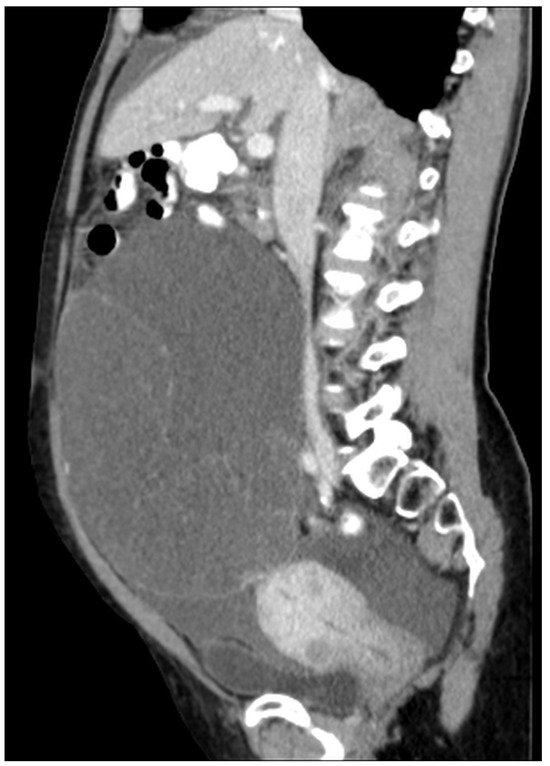

Figure 1. Mucocele of the appendix (arrow) (CT, venous phase, sagittal plane). There is cystic dilatation of the appendix behind the ascending colon. There is no evidence of perforation or the presence of mucin outside the mucocele.

Mucocele of the appendix refers to a dilated mucin-containing appendix. This term is mainly used by clinicians and radiologists (Figure 1, Figure 2, Figure 3 and Figure 4). It is necessary to distinguish “true mucocele” from a mucinous adenoid neoplasm [7]. The term mucocele was first used by Karl Freiherr von Rokitansky in 1842. Two years later, Werth used the term pseudomyxoma peritonei [4]. The clinical signs are minimal or often completely absent. The rupture of the mucocele can also be asymptomatic. Mucocele may be found on ultrasound or via a regular gynecological examination. A CT scan confirms the diagnosis. Treatment consists of the surgical removal of the dilated appendix, often together with the surrounding part of the cecum (Figure 5, Figure 6 and Figure 7). This approach is curative if there is no rupture or presence of tumor cells on the peritoneal surface. The diagnosis is confirmed through pathological examination of the specimen (Figure 8).